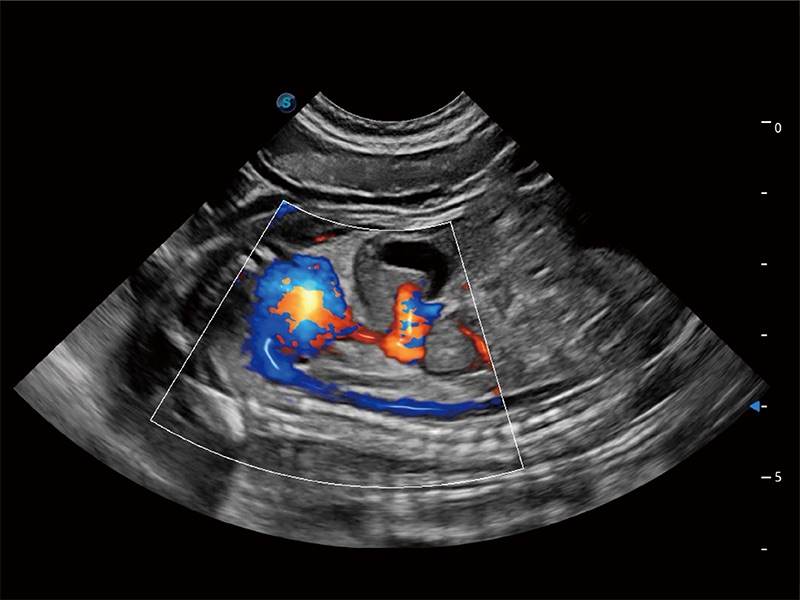

非线性融合造影成像充分利用谐波和基波信号,为难以观察的血流进行增强显像。可用于线阵、凸阵、微凸阵、相控阵探头。